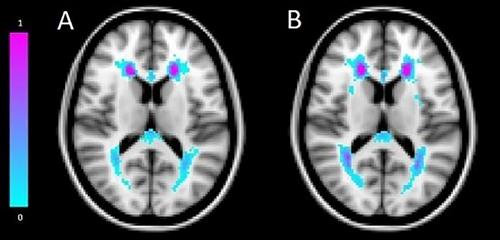

Baseline data (2011–2015) were collected from 562 participants of Moroccan, South-Asian Surinamese, and Dutch descent, with 3 Tesla brain MRIs conducted between 2021 and 2022 (median follow-up 8.4 years). Brain and WMH volumes were assessed using automated segmentation of Magnetization Prepared—RApid Gradient Echo and three-dimensional Fluid-Attenuated Inversion Recovery scans. Linear regression analyses examined associations between cardiovascular risk factors and brain volumes and log-transformed WMH volumes. Interaction terms explored ethnic differences in these associations.

Median age was 53 years, and 45% were female. Higher body mass index (BMI) and diabetes mellitus were associated with lower brain volumes (−7.6 mL per BMI unit, 95% confidence interval [CI] −12.6, −2.7; 103.4 mL for diabetes, 95% CI −167.4, −39.3). Hypertension and a history of cardiovascular disease were associated with 54.7% (95% CI 25.5, 90.7) and 98.3% (95% CI 30.9, 200.4) higher WMH volumes, respectively. Associations of diabetes with brain volume and hypertension with WMH volume were most pronounced among South-Asian Surinamese participants.